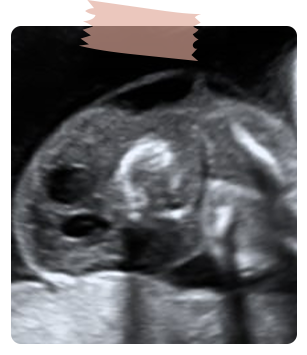

Cardiopatia congénita más frecuente, hay un defecto interventricular, generalmente perimembranoso, aorta que cabalga sobre el septum interventricular.

En el corte de 3 vasos se puede diferenciar si hay estenosis, atresia o ausencia válvula pulmonar